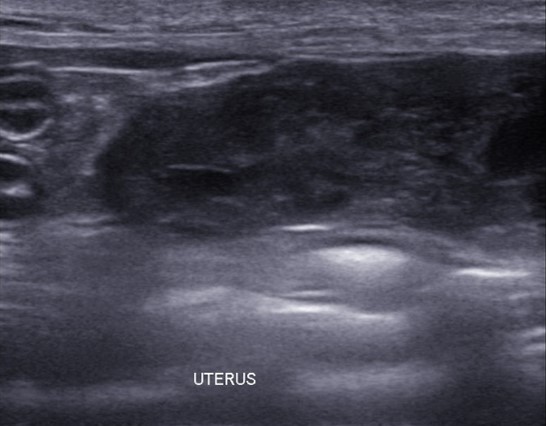

이어 진행된 초음파 검사에서는 자궁축농증으로 인해 내막이 두꺼워지고 크기가 커지는 염증성 변화가 진행되고 있었습니다.

✔US 양 자궁내막증식, 자궁각내삼출물에 의한 심한 확장소견